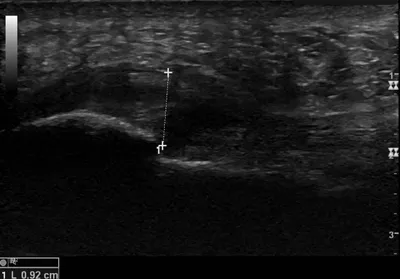

This collection contains 3 radiology images related to plantar fascia, including various imaging modalities such as X-rays, MRIs, CT scans, and ultrasound images commonly used in medical diagnosis and education.